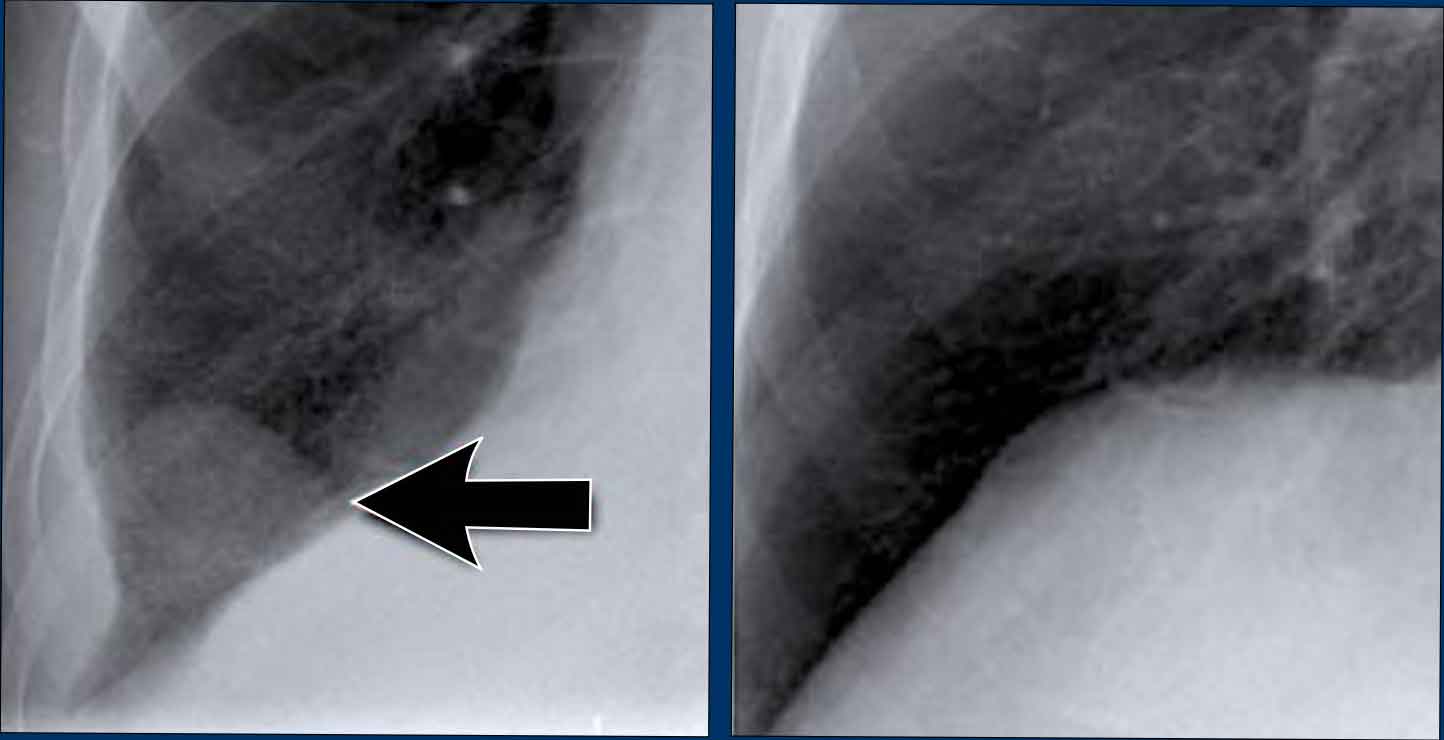

Pleural Plaques (Asbestos-Related)

• Multiple irregular pleural opacities are seen.

• Some follow the contours of the chest wall (arrows).

• Typical features of asbestos-related pleural plaques:

• Bilateral, extensive

• Often involve the diaphragmatic domes

Unilateral calcified pleural opacities may indicate: